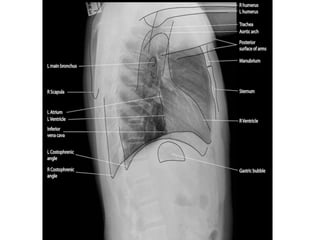

Normal Chest X-Ray

Scheme of viewing PA film

1. Request form                Name ,age, sex, date, clinical information

2. Technical                   View

Centering, patient position

Side Markers

Adequate inspiration

Exposure/Penetrance

3. Soft tissue and bony cage   Subcutaneous emphysema, fractures

4.Trachea                      Position, Outline

5. Heart and Mediastinum       Shape , Size, Displacement

6.Diaphragms                   Outline ,Shape , Relative position

7.Pleural spaces               Position of horizontal fissure,

costophrenic and cardiophrenic angles

8.Lungs                        Local , generalized abnormalities,

comparison of translucency and vascular

marking sof the lungs

9.Hidden areas            Apices, Posterior sulcus, Mediastinum,

Hila, Bones

10. Hila                  Density, Position, Shape

11. Below the Diaphragm   Gas shadows, Calcification